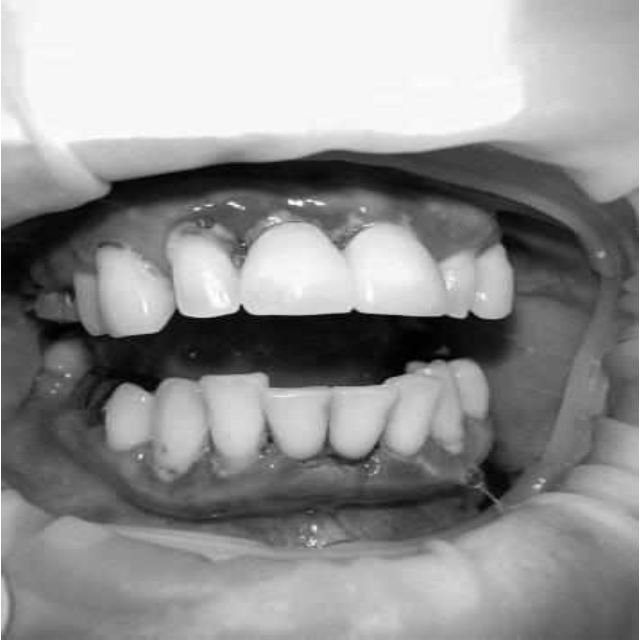

Ранее у пародонтолога не наблюдалась. При осмотре выявлены: неудовлетворительная индивидуальная гигиена полости рта, пародонтальные карманы до 7 мм, обильная кровоточивость и гноетечение из пародонтальных карманов, подвижность зубов 4.2, 4.1, 3.1, 3.2 II степени, обильные над- и поддесневые зубные отложения (рис. 1). На ортопантомограме отмечается резорбция костной ткани до ½ длины корня, очаги остеопороза (рис. 2). Пациенту был поставлен диагноз хронический генерализованный пародонтит тяжелой степени тяжести. При осмотре была составлена пародонтограмма с использованием компьютерного зондирования (рис. 3).

Рис. 3. Пародонтограмма с использованием компьютерного зондирования при первичном обращении

Через 6 месяцев при осмотре выявлен удовлетворительный уровень индивидуальной гигиены, отсутствие участков кровоточивости и гноетечения (рис. 4), пародонтальные карманы уменьшились в размерах (рис. 5). Пациент отмечает значительные улучшения. После стабилизации пародонтологического статуса пациент направлен для дальнейшего ортопедического лечения.

Рис. 5. Пародонтограмма с использованием компьютерного зондирования через 6 месяцев